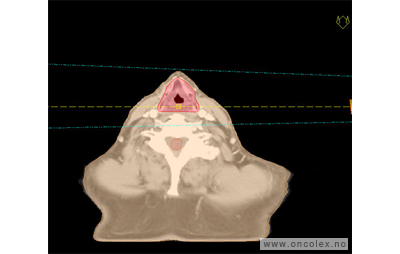

Skisse over hvordan strålefeltet planlegges:

Illustrasjon for målvolum

• GTV (Gross Tumor Volume): Identifisert tumor.

• CTV (Clinical Target Volume) GTV + omkringliggende vev hvor det kan væremikroskopisk spredning.

• ITV (Internal Target Volume): CTV + en indre margin som tar hensyn tilindre bevegelser og endringer av CTV.

• PTV (Planning Target Volume): Innstillingsmargin som inneholder ITV og samtidig tar hensyn til antatte pasientbevegelser, samt variasjoner i pasientopplegging og feltinnstillinger.

• Feltgrense. Tegnes som oftest på kroppen.

ICRU (International Commission on Radiation Units and Measurements)